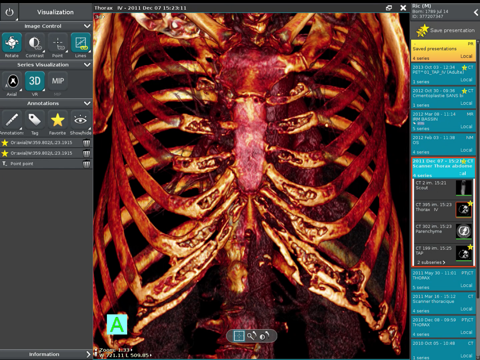

Anywhere Streaming is a DICOM visualization client that connects to Anywhere Server. It provide standard medical image navigation tools surch as : slicing, windowing, MPR, 3D VR, MIP, oblique ... All standard medical image modalities are ...